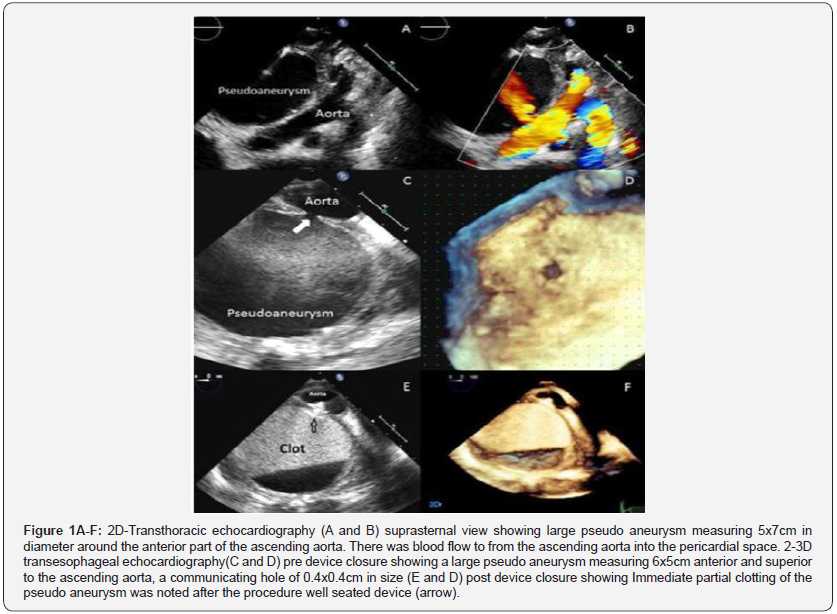

A 16 year old girl with asymptomatic severe mitral regurgitation underwent surgical mitral valve repair with no immediate complications. During the same admission, however, the patient was observed to have poor wound healing and she developed sternal wound infection and wound gapping which was treated with antibiotics and surgical debridement. Transthoracic echocardiography (TTE) showed evidence of infective endocarditis with a large vegetation on the mitral valve so antibiotic treatment prolonged. While she is stay for infective endocarditis, she developed fever, tachycardia and hypotension. Her hemoglobin level dropped from 11.5 to 8.7gram/dl. A chest x-ray showed a widening of the mediastinum. TTE showed a large pseudoaneurysm measuring 5x7cm in diameter around the anterior part of the ascending aorta. There was blood flow to and from the ascending aorta into the pericardial space (Figure 1A & 1B). The pseudoaneurysm was thought to be arising from the cardioplegia needle site which was sutured after surgery but developed dehiscence of the sutures later due to infective endocarditis. The patient was given a blood transfusion. The patient’s condition was discussed and it was decided for an urgent intervention due to the significant hemoglobin drop and to avoid the risk of pseudoaneurysm rupture and death. Due to the high risk of surgical repair, an attempt of transcatheter closure of the pseudoaneurysm was planned. Two and three-dimensional transesophageal echocardiography (TEE) was performed and showed a large pseudoaneurysm measuring 6x5cm anterior and superior to the ascending aorta, a communicating hole of 0.4x0.4cm in size with bidirectional flow was noted (Figure 1C & 1D). The opening of the pseudoaneurysm was successfully closed using a 4x4mm Amplatzer Duct Occluder II device (9- PDA2-04-04 St. Jude Medical, Inc. St. Paul, MN) which was delivered via a 5Fr sheath. Post-procedure TEE showed that the device was well seated with no residual communication between the pseudoaneurysm and the ascending aorta. Immediate partial clotting of the pseudoaneurysm was noted after the procedure (Figure 1E & 1F). The patient was kept in the hospital to complete the treatment for infective endocarditis. However, twenty days later TTE showed another new pseudoaneurysm at the aortic cannula site. The prior device was seen at the site of previous pseudoaneurysm with no residual leak. An urgent Computerized Tomographic (CT) angiogram was done and revealed another aortic pseudoaneurysm surrounding the ascending aorta at the aortic cannula site, while the previous device was seen in position (Figure 2A & 2B).